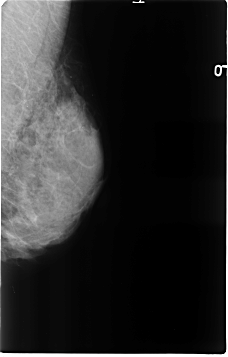

ics_version 1.0 filename B-3120-1 DATE_OF_STUDY 16 11 1994 PATIENT_AGE 50 FILM FILM_TYPE REGULAR DENSITY 4 DATE_DIGITIZED 25 2 1998 DIGITIZER LUMISYS LASER SEQUENCE LEFT_CC LINES 4624 PIXELS_PER_LINE 2976 BITS_PER_PIXEL 12 RESOLUTION 50 NON_OVERLAY LEFT_MLO LINES 4632 PIXELS_PER_LINE 2960 BITS_PER_PIXEL 12 RESOLUTION 50 NON_OVERLAY RIGHT_CC LINES 4616 PIXELS_PER_LINE 2960 BITS_PER_PIXEL 12 RESOLUTION 50 OVERLAY RIGHT_MLO LINES 4656 PIXELS_PER_LINE 2992 BITS_PER_PIXEL 12 RESOLUTION 50 OVERLAY |